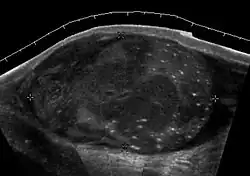

Patients with testicular lymphoma are usually old aged around 60 years of age, present with painless testicular enlargement and less commonly with other systemic symptoms such as weight loss, anorexia, fever and weakness. Bilateral testicle involvements are common and occur in 8.5% to 18% of cases. At sonography, most lymphomas are homogeneous and diffusely replace the testis [Fig. 7]. However focal hypoechoic lesions can occur, hemorrhage and necrosis are rare. At times, the sonographic appearance of lymphoma is indistinguishable from that of the germ cell tumors [Fig. 8], then the patient's age at presentation, symptoms, and medical history, as well as multiplicity and bilaterality of the lesions, are all important factors in making the appropriate diagnosis.